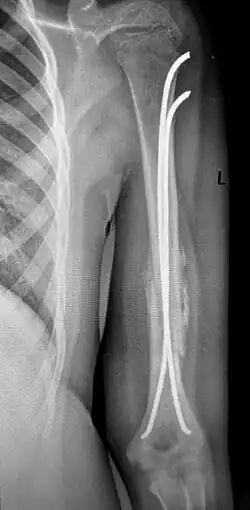

Рентгенограмма при диафизарном переломе плеча. Переломы плеча в среднем отделе (диафизарные переломы плеча) возникают в результате падения на руку или удара по плечу, могут быть косыми, поперечными, винтообразными и оскольчатыми. Диафизарные переломы плеча нередко сочетаются с повреждением лучевого нерва. Возможно повреждение плечевых артерий и вен.

- Симптомы

Клиническими признаками перелома плеча являются боли, отёчность, деформация, крепитация костных фрагментов и патологическая подвижность плечевой кости. При переломах плеча с повреждением лучевого нерва пациент не может самостоятельно разогнуть пальцы и кисть. Для уточнения диагноза и выбора тактики лечения выполняют рентгенографическое исследование.

- Лечение

Переломы плеча без смещения фиксируют гипсовой лангетой, с последующей её заменой на закрытую повязку типа «Дезо» или «Вильпо». При этом контролируется сопоставление отломков с помощью рентгенограмм в разных проекциях. Общий срок иммобилизации при консервативном лечении диафизарных переломов плечевой кости составляет 3-3,5 месяца.

Консервативное лечение целесообразно только в редких случаях: при переломах без смещения или при минимальном смещении отломков, а также при возникновении противопоказаний к операции. В остальных случаях показано оперативное лечение, так как современные малоинвазивные и другие методы фиксации позволяют уже через 3-4 недели начинать разработку движений в плечевом и локтевом суставах, что в свою очередь, предупреждает возникновение тяжёлых контрактур в этих суставах. При повреждении лучевого нерва вследствие перелома проводят оперативное лечение с обязательной ревизией нерва, с адекватной фиксацией отломков.

Хирургическое лечение также показано при многооскольчатых переломах плеча, невозможности закрытой репозиции, интерпозиции мягких тканей и повреждении сосудов и нервов. Фиксацию отломков осуществляют при помощи пластин, интрамедуллярных штифтов с блокированием, или аппарата Илизарова.